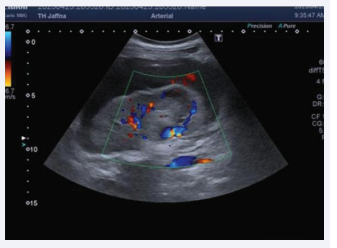

Ultrasound Scan of the abdomen depicted large intracapsular haematoma with a small aneurysm in the inter polar region of right kidney (Figure 1, 2). Ultrasound excluded any uterine bleeding or focus of infection.

Ultrasound Scan of the abdomen.

Figure 1: Ultrasound Scan of the abdomen.